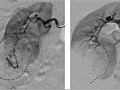

In some cases, a method called interventional radiology may be used during an angiogram to treat diseases. For example, a catheter can be used to open a blocked blood vessel, deliver medicine to a tumor, or stop intestinal bleeding caused by diverticular hemorrhage. To stop intestinal bleeding, the catheter is moved into the small artery where the bleeding is occurring, and medicine that narrows the artery or causes the blood to clot is injected through the catheter.

Blood vessels that are not in their normal position may mean that a tumor or other growth is pushing against them.

A narrow spot in an artery may mean that a fat deposit, calcium deposit, or clot is reducing blood flow through the blood vessel.

A bulge in a blood vessel may mean a weakness in the blood vessel wall (aneurysm).

Dye that leaks out of a blood vessel may mean a hole in the blood vessel.

An abnormal pattern of blood vessels may mean that a tumor is present.